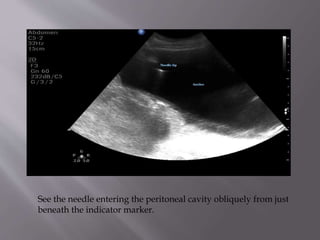

Here we clearly see free fluid in Morrison's pouch that extends

superiorly around the liver

See the needle entering the peritoneal cavity obliquely from just

beneath the indicator marker.